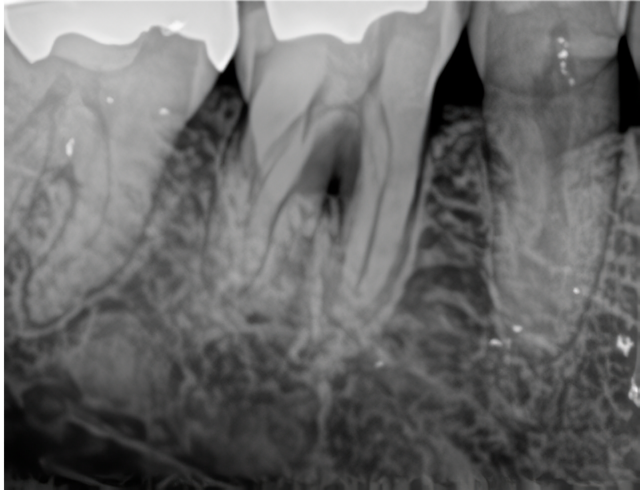

歯周病で失った骨を取り戻す歯周組織再生治療

とみい歯科医院では、歯周病で失われた歯槽骨を再生する先進的な外科治療を導入しています。この方法では歯周組織再生剤「リグロス®」を根分岐部などの患部に注入し、歯槽骨の再生を促します。

例えば、歯周ポケット6mmの根分岐部病変が、治療後には3mmまで改善した症例があります。透明なジェル状のリグロスは注入部の毛細血管新生を促進し、骨再生を助けます。この健康保険適用の治療により歯周病の再発を抑制し、歯の長期保存に貢献します。

同医院では、リグロス®の効果を最大限に引き出すため、患者様の状態に応じて精密な診断と計画を行っています。治療にあたっては、歯周病専門医が丁寧なカウンセリングを行い、適応の有無や治療のリスク・予後についてもしっかりと説明しています。

また、歯周組織再生療法は歯周外科の中でも高度な技術が求められるため、専門的な知識と経験が重要です。同医院では、豊富な実績と最新の設備をもとに、患者様にとって最適な再生治療の提供を目指しています。